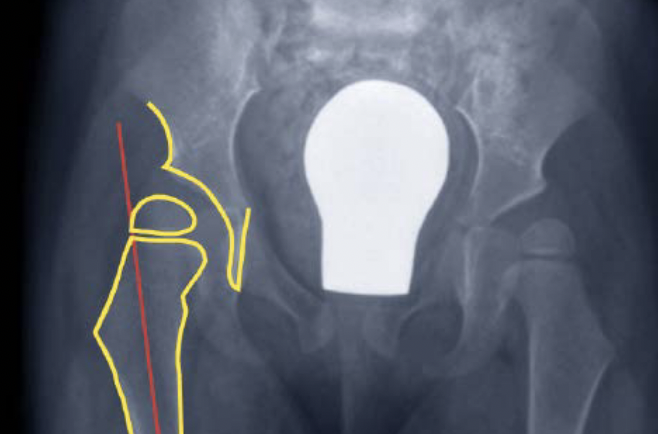

Salter Redirectional Osteotomy

Indication

Anterolateral acetabular deficiency with concentric acetabular shape

Younger patient < 8 years - osteotomy rotates through flexible pubic symphysis

Technique

Osteotomy

- through greater sciatic notch to between ASIS and AIIS

- Gigli saw passed around greater sciatic notch

- osteotomy posterior to anterior

- acetabulum rotated anteriorly and laterally

- 15 mm triangular graft from iliac crest apophysis

- secure with K wire fixation

Salter complete osteotomy